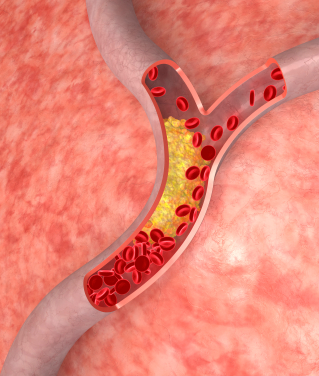

• Maintaining healthy cholesterol levels

• Keeping blood pressure down

• Regulating blood sugar levels

Although these seven steps have been shown to reduce your risk for heart disease, now these seven steps have also been shown to slash your risk for cancer.

In order to be healthy, you need to take certain steps to reduce your risk for cancer, diabetes, heart disease, and other chronic diseases.

By including these simple – yet effective – lifestyle changes, not only could you reduce your risk for a heart attack, but you may also reduce your risk for a number of different cancers.